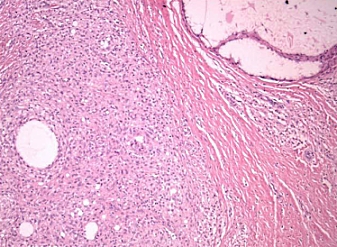

When the doctors examined the swelling in the man's thigh they discovered the probably cause of the swelling: They found foreign body giant cells: immune cells that are often found where foreign material has entered the body. The immune system uses the foreign body giant cells to engulf the alien cells. The bodybuilder's foreign body giant cells can be seen in the photo below.

The cavities you see contain "obvious foreign material" as Weinreb calls it. He suspects that the foreign material entered the body with the steroids injections.